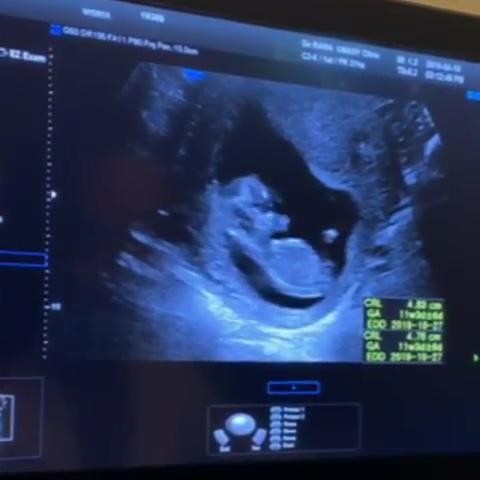

이어 뱃 속의 아기가 움직이는 모습을 담은 초음파 영상까지 공개해 눈길을 끌었다.